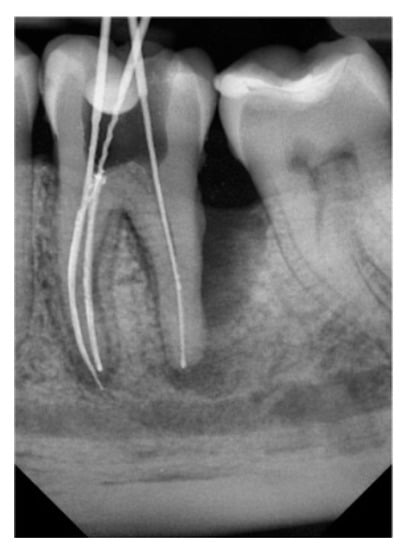

| Number of Tooth | 36 | 36 | 37 | 36 | 36 | 27 | Average Volume B/A (mm³) |

| Volume before treatment (mm³) | 654.4 | 650 | 498 | 300 | 220 | 205 | |

| Volume after treatment (mm³) | 309 | 260 | 220 | 140 | 110 | 115 | 421.23/192.3 |

| Change in percent (%) | 52.8 | 60 | 65 | 53 | 50 | 44 |

| Number of Tooth | 46 | 47 | 36 | 37 | 16 | 27 | Average Volume B/A (mm³) |

| Volume before treatment (mm³) | 287.3 | 450 | 650 | 700 | 300 | 520 | |

| Volume after treatment (mm³) | 207.1 | 310 | 400 | 580 | 245 | 360 | 484.55/350.4 |

| Change in percent (%) | 28 | 31 | 38 | 17 | 18 | 30.7 |

| Group | Amount of Teeth | Average | SD | ST p | M-W p |

|---|---|---|---|---|---|

| 1 | 6 | 192.3 | 83.0 | ||

| 2 | 6 | 350.4 | 133.1 | 0.033 | 0.037 |